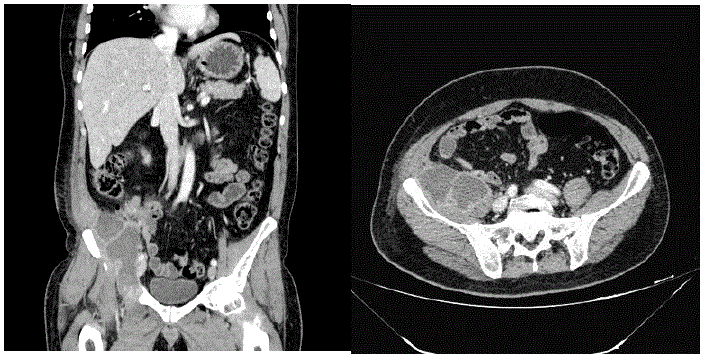

Homem, 59 anos de idade, foi vítima de atropelamento por automóvel com velocidade estimada em 40km/h. Admitido no serviço com:

A: via aérea pérvia, saturação de 97% ar ambiente

B: ausculta e expansibilidade pulmonar simétricas

C: FC: 80bpm, PA: 110 x 70mmHg

D: Glasgow de 15. Sem alterações de pupilas

E: Dor abdominal na fossa ilíaca direita e supra-púbica. Presença de hematúria.

Dor na região coxo-femoral direita com deformidade do membro inferior direito.

Realizada tomografia do abdome com os seguintes achados:

Qual é a melhor conduta no trauma abdominal?